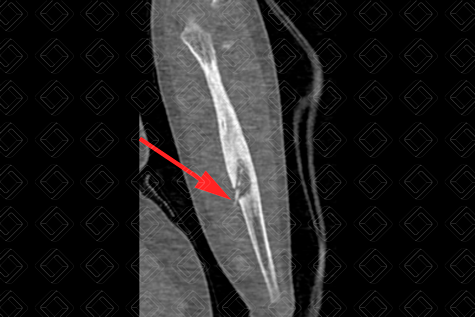

Descrição da figura 3: Tomografia computadorizada do antebraço esquerdo no plano sagital. Ulna com espessamento difuso da sua cortical óssea, com rompimento da mesma e sequestro ósseo (seta vermelha).